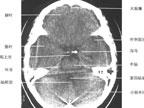

头颅ct解剖图

正常头颅ct解剖图